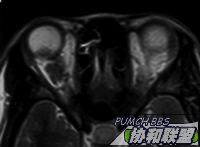

患者女性30岁。主诉右眼视力下降半年。检查右眼视力眼前手动,眼前节正常。眼底见后极部颞侧实性隆起,周边浅层网脱。超声及MRI见图。全身检查未发现明显异常。

MRI  T1 & T2

图片点击可在新窗口打开查看